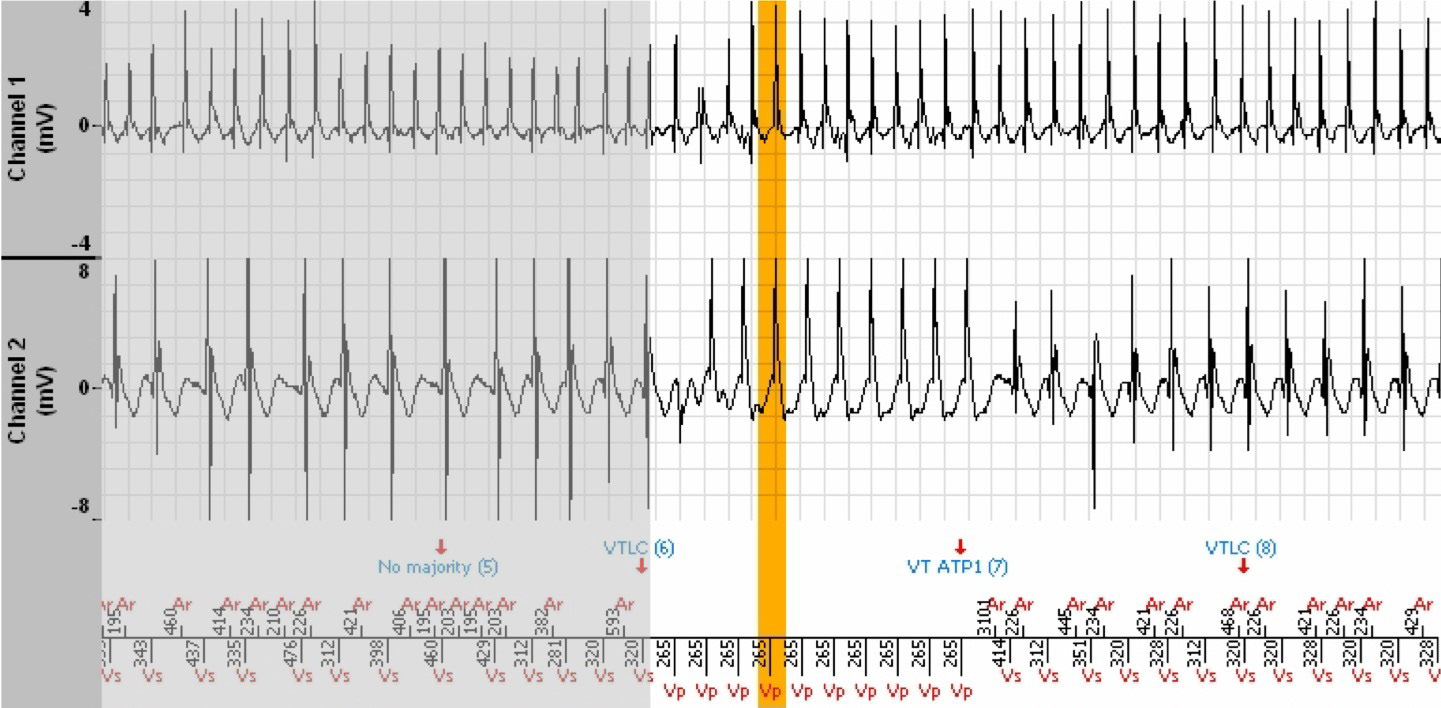

The episode lasted 7 minutes and 38 seconds and the tachogram below shows only the last 3 minutes. During the preceding 4 minutes 30 seconds, the ventricular rate is perfectly stable in the Slow VT zone.

EGM

- Then, suddenly, the rhythm becomes unstable (starting at the orange vertical bar) with cycles whose coupling interval is in the Slow zone (non Tachy) for at least 3 out of 8 cycles (but less than 6), which leads to annotation n°5 « No majority ». This majority maintains the VT persistence counter (no reset to zero, no increment).

- Then appears an acceleration in rate which leads the tachycardia into the VT zone (annotation n°6). The incrementation of the VT persistence counter had begun during the Slow VT phase, and the VT counter reached the programmed persitence shortly

thereafter. The persistence being reached and the average rate of the last 4 Tachy/VF cycles in the VT zone induce a VT zone ATP (annotation n°7).

- Indeed, annotation n°4 revealed a diagnosis of VT in the VT zone that had begun to increment the VT persistence counter.

- The ATP does not terminate the tachycardia, which returns to the Slow VT zone with perfect stability, with no defibrillator intervention for the remaining 3 minutes, until the sudden slowing of the rate and termination of the episode.